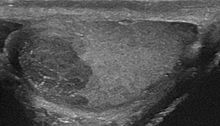

Ultrasound image of a seminoma

Intratesticular masses that appear suspicious on an ultrasound should be treated with an inguinal orchiectomy. The pathology of the removed testicle and spermatic cord indicate the presence of the seminoma and assist in the staging. Tumors with both seminoma and nonseminoma elements or that occur with the presence of AFP should be treated as nonseminomas. Abdominal CT or MRI scans as well as chest imaging are done to detect for metastasis. The analysis of tumor markers also helps in staging.[10]